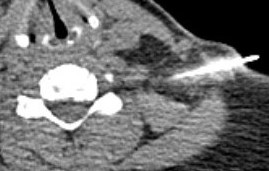

CT

May add complementary information to MRI

- posterolateral impingement from uncovertebral spur

- ossification of the PLL

- transforaminal injections with CT

- interlaminar injections with CT